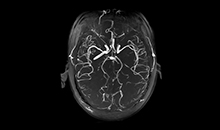

高均匀度磁体

呈现大FOV、偏中心优质图像;实现大范围压脂成像,缩短压脂序列时间